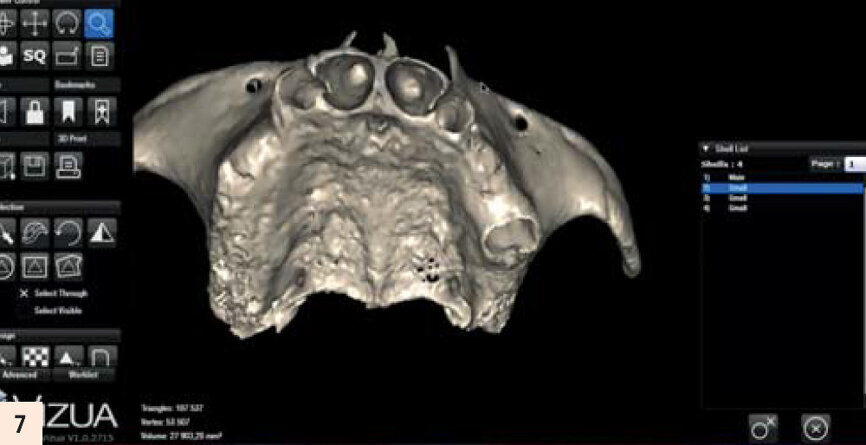

Modélisation par Vizua du modèle denté...

...et avec des extractions virtuelles.

L’important est de reproduire par l’empreinte en fin de chirurgie, l’occlusion enregistrée des semaines auparavant. La technique utilisée sera l’empreinte fractionnée, grâce à une gouttière callée sur des repères fixes que nous retrouvons en fin d’intervention (Fig. 5). Cette méthode a été décrite par Luc Gillot et Bernard Cannas qui font partie des pionniers de la MCI en France.9, 11 Ce cas clinique est complexe. Comme toute chirurgie, nous n’avons pas le droit à l’erreur. La planification sur ordinateur a permis de se familiariser avec les volumes osseux. Simuler la chirurgie permettrait d’éviter les pièges d’une anatomie complexe. En partenariat avec l’équipe Vizua et la Sapo implant, nousimprimons le maxillaire de notre patiente en individualisant les dents pour visualiser les alvéoles d’extraction (Figs. 6 et 7). Puis nous procédons au forage dans ce modèle imprimé en résine, en suivant notre planification. Nous appréhendons les difficultés de ce cas : la fine corticale du bloc incisif, la position exacte de l’implant en 15 dans la paroi antérieure du sinus droit... Quelle meilleure préparation que la simulation sur modèle ? (Fig. 8)